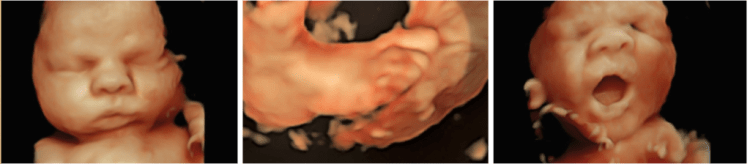

Al igual que los ultrasonidos regulares, los ultrasonidos 3D y 4D usan ondas de sonido para crear una imagen de su bebé en su útero. La diferencia es que los ultrasonidos 3D crean una imagen tridimensional de su bebé, mientras que los ultrasonidos 4D crean un efecto de video en vivo, ultrasonido 4D como una película: puede ver a su bebé sonreír o bostezar.

Los padres a menudo quieren ultrasonidos 3D y 4D. Te permiten ver la cara de tu bebé por primera vez. A algunos médicos les gustan las ecografías 3D y 4D porque pueden mostrar ciertos defectos congénitos, como el paladar hendido, que podrían no aparecer en una ecografía estándar.